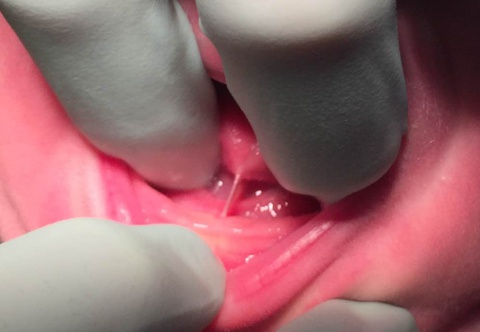

Type 3 Ankyloglossia